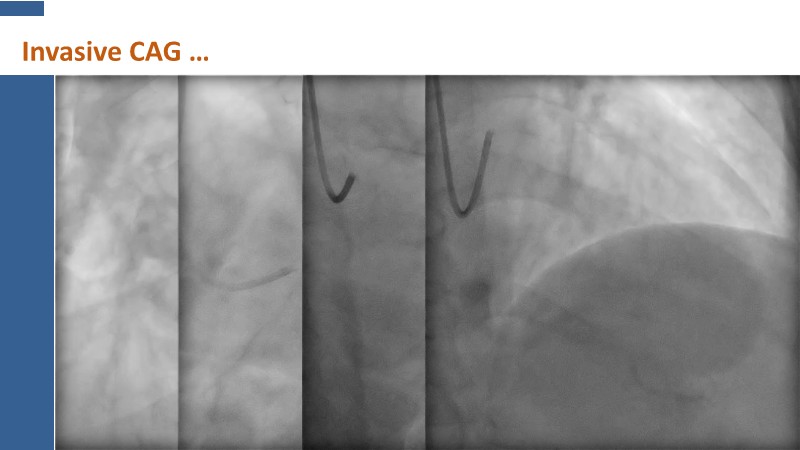

This session explores how near-infrared spectroscopy (NIRS) is redefining PCI by revealing what angiography cannot see. By identifying lipid-rich and vulnerable plaques, NIRS helps anticipate procedural risk and refine decision-making before stent implantation. The session shows how plaque composition, rather than calcium alone, can guide lesion preparation strategies, support safer stent positioning, and improve expansion. Through practical examples, it highlights how integrating NIRS with intravascular imaging and physiology moves PCI toward a more targeted, data-driven, and truly precision-based approach.

- To identify vulnerable plaques: NIRS detects lipid-rich plaques that are invisible to angiography. This allows interventionalists to anticipate complications like distal embolisation or no-reflow and adjust their approach accordingly